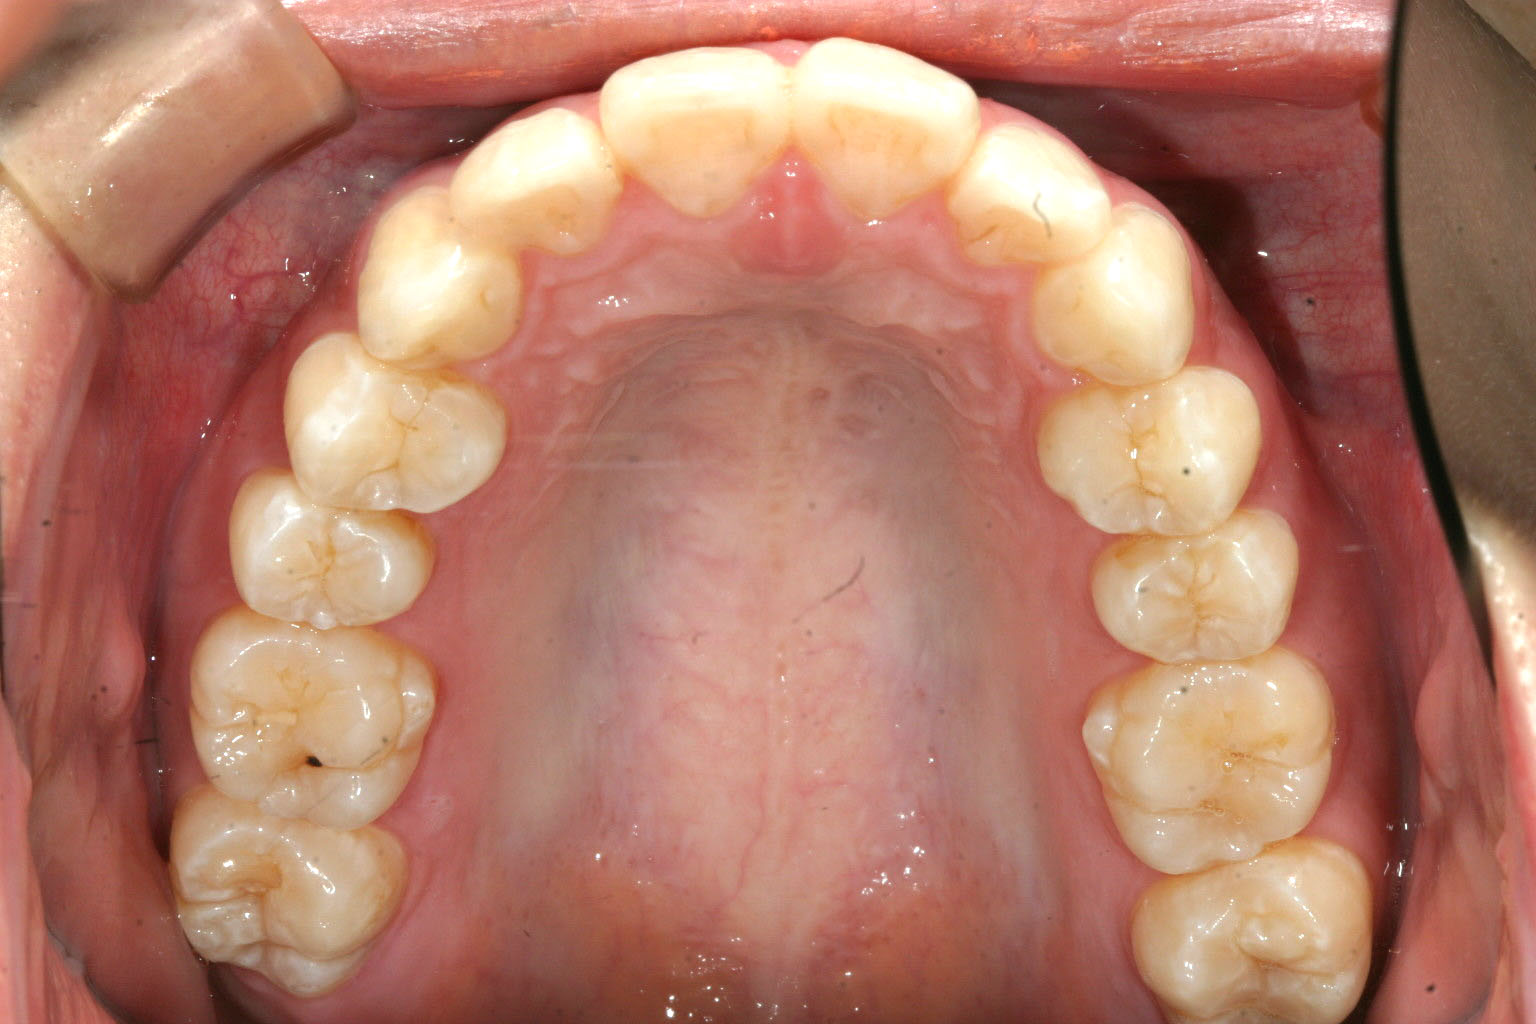

歯列だけ見れば綺麗なんですが、、、

左右小臼歯の抜歯を行い矯正行いました。

下顎はそのまま歯列を整えました。